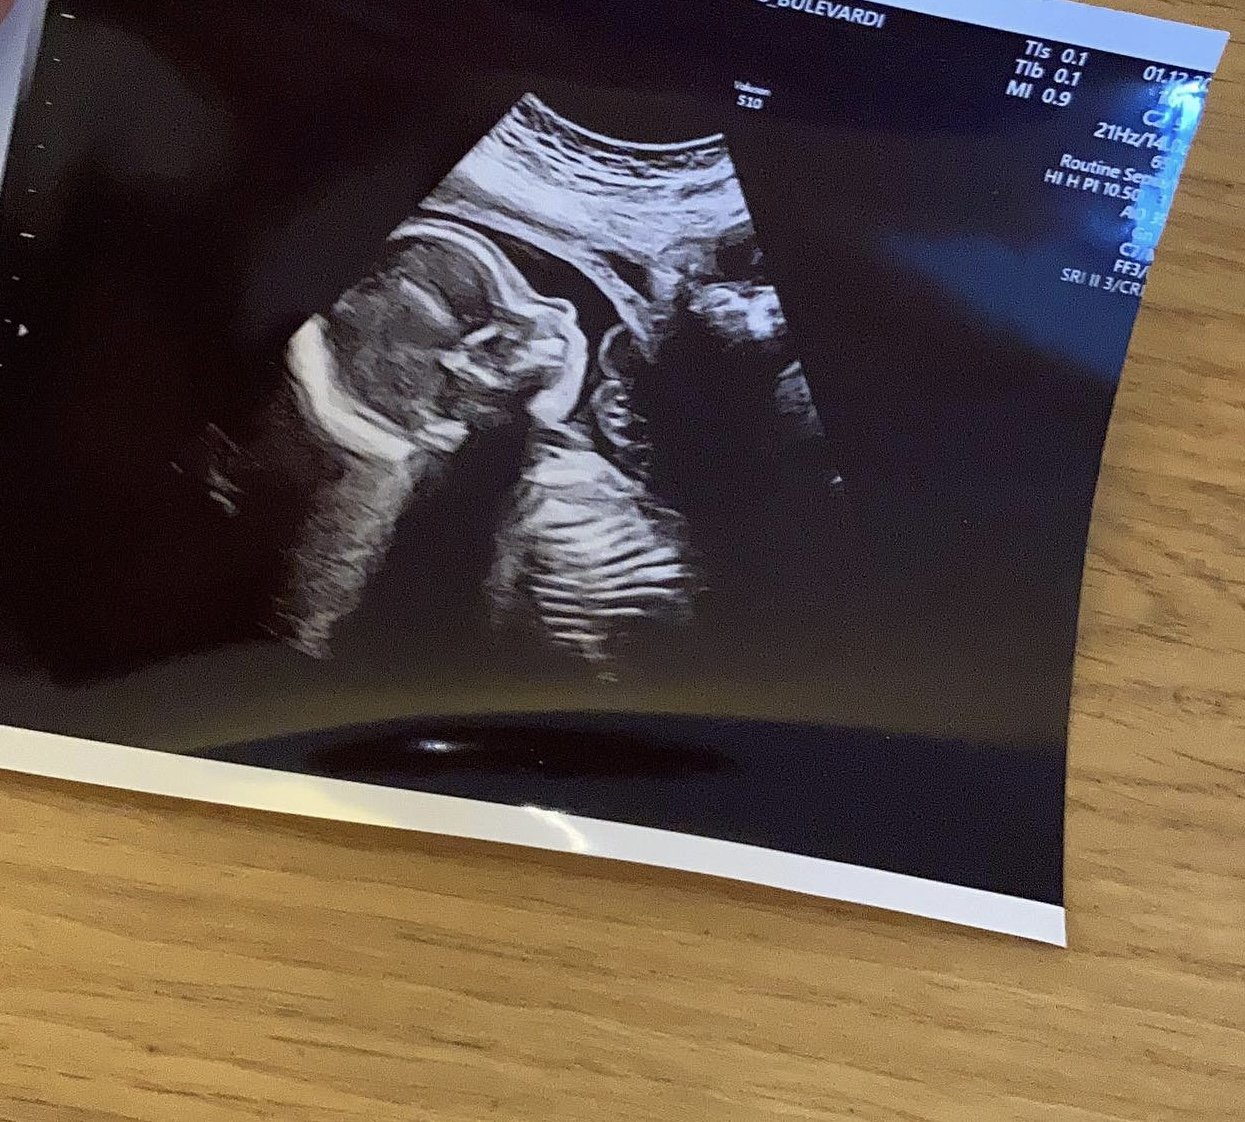

21. raskausviikko: toinen ultra, edelleen kaikki hyvin!

1.12. (20+3) Toinen ultra meni hyvin, kaikki oli hyvin. Siisti huuli, aivot, sydän (laskimo valtimo), mittasuhteet, munuaiset, kohdun paikka, jaloissa ei kampuraa.

Hirveän helpottunut olo. Että me nyt ihan oikeasti saadaan tämmöinen meille.

Se potki lujaa, välillä vähän vilkutteli kädellään siihen malliin, että menkääs siitä kyyläämästä moikka.